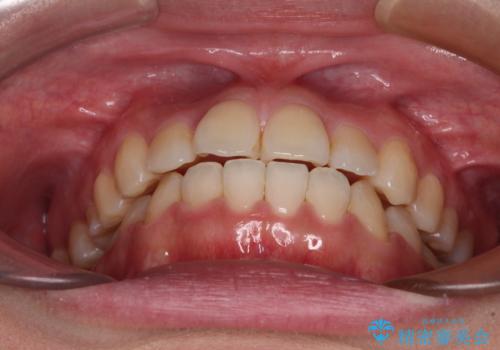

- 前歯のデコボコとクロスバイトを気にして来院された患者様です。

骨格的に下顎が前方位の受け口傾向であり、それが原因でクロスバイトとなっていました。

反対咬合とクロスバイトを改善して噛みやすい咬合に